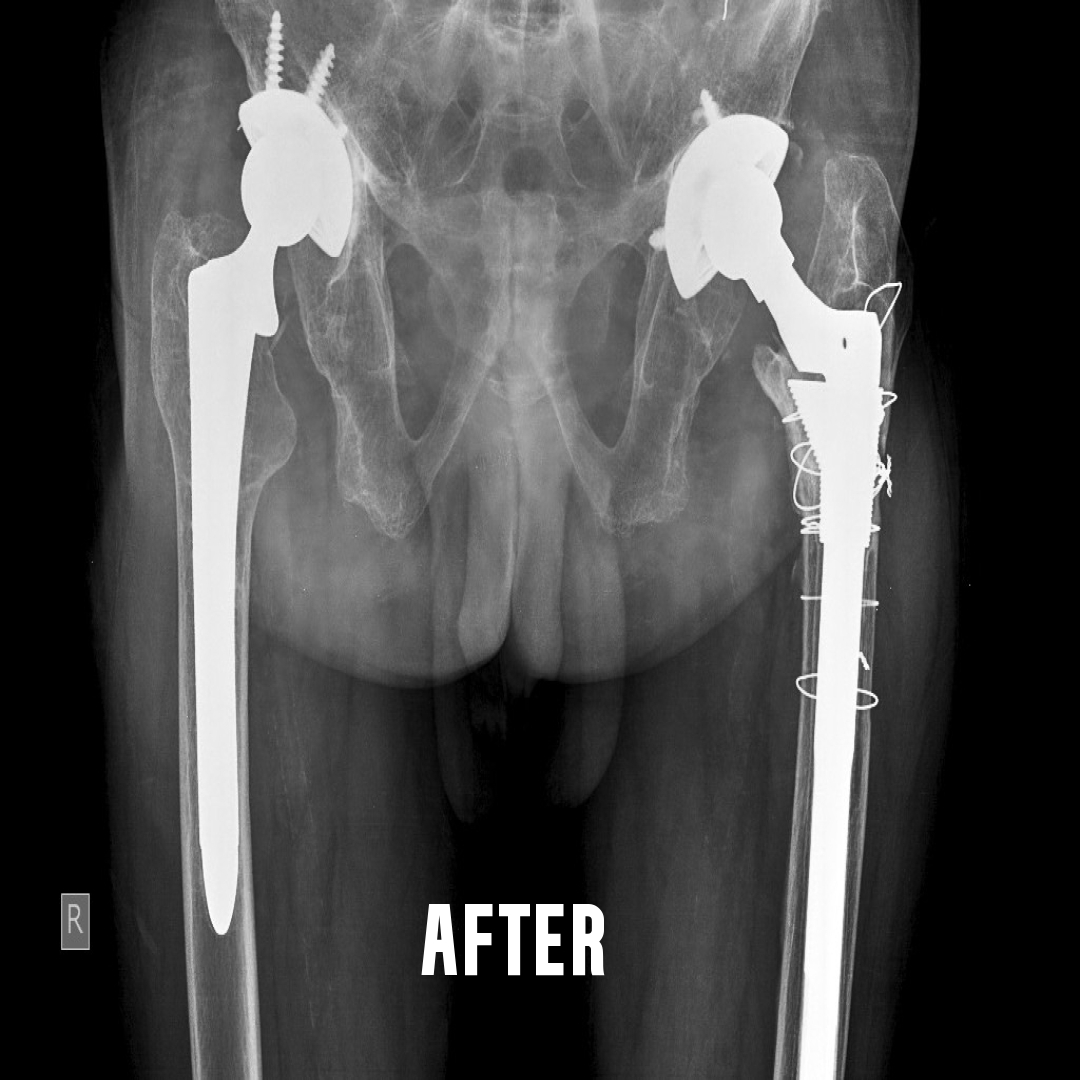

This is a surgery where both the ball and socket of the hip joint are replaced with artificial materials.

The normal hip joint consists of a cup called the acetabulum into which articulates a head of the thigh bone called the femur.

This joint may become damaged due to a variety of conditions. The common

causes are rheumatoid arthritis, ankylosing spondylitis, childhood diseases

like perches, injury to the hip joint etc. There is loss of articular cartilage, a

smooth lining of the ends of the bone in a joint. The result is that raw bones rub against each other causing pain. This condition where the articular

cartilage is damaged, is collectively called arthritis.

Damage to hip joint can occur at any age. Total hip replacement can be done

after the age of 20 years...Learn More

Done for failed joint replacement due to infection, aseptic loosening, fracture around the implant etc. The surgery is more complicated, and the results depend on intense post operative

physiotherapy. Surgery is undertaken after thorough examination, adequate investigations regarding the cause of the failure and after a detailed interview with the patient and his relatives.

Infected replacement revisions are done as two stage procedure. Fix up an appointment if you need further information